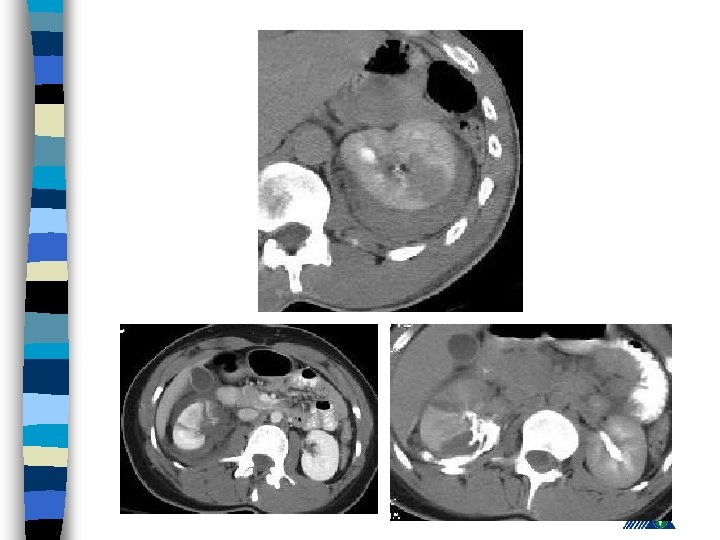

Renal Trauma n Blunt : (85 -90% ) – vehicle accident, fall, rapid deceleration, iatrogenic n Penetrating : Gunshot and (85 -90 % associated with intraabdominal or thoracic injury)

Renal Trauma - Diagnosis History n PE (lumbar echimosis, pain with palpation) n Hematuria n – (Renal vascular injury - 36 % not associated with hematuria) n Variable clinical presentation (asymptomaticshock)

Radiologic Imaging n n n KUB (loss of psoas or renal contour) IVU (delayed renal function, nonhomogenous collecting system) USG (lumbar hematoma and urinoma lokalizasyonu) Computerized Tomography Renal angiography

American Association for the Surgery of Trauma Organ Injury Severity Scale for the Kidney Grade Tip Tanım 1 kontüzyon Mikroskobik ya da gross hematuri, ürolojik incelemeler normal hematom Sub. Kapsuler, genişlemeyen parankimal hasar yok hematom Genişlemeyen perirenal hematom , renal retroperitona sınırlı laserasyon <1 -cm derinlikte parenkimal korteks hasarı, üriner ekstravazasyon yok 3 laserasyon >1 -cm derinlikte parenkimal korteks hasarı, üriner ekstravazasyon yok 4 laserasyon Medulla ve toplayıcı sisteme ulaşan parenkim hasarı vasküler Renal arter ve vende hemoraji içeren hasar laserasyon Tamamen parçalanmış Böbrek vasküler Renal hilusun ayrılması 2 5

Expectant Management: n Hemodynamically stable, well defined and non-expanding injury on CT scan n 88 % patienst are observed n If there is associated gross hematuria, admit and observe

Surgery : Absolute Indication – Persistant renal bleeding – Expanding perirenal hematoma – Perirenal hematoma with pulsation n Relative indication – Urinary extravasation – Inability in proper staging – Delayed arterial injury – Canlı olmayan doku varlığı n